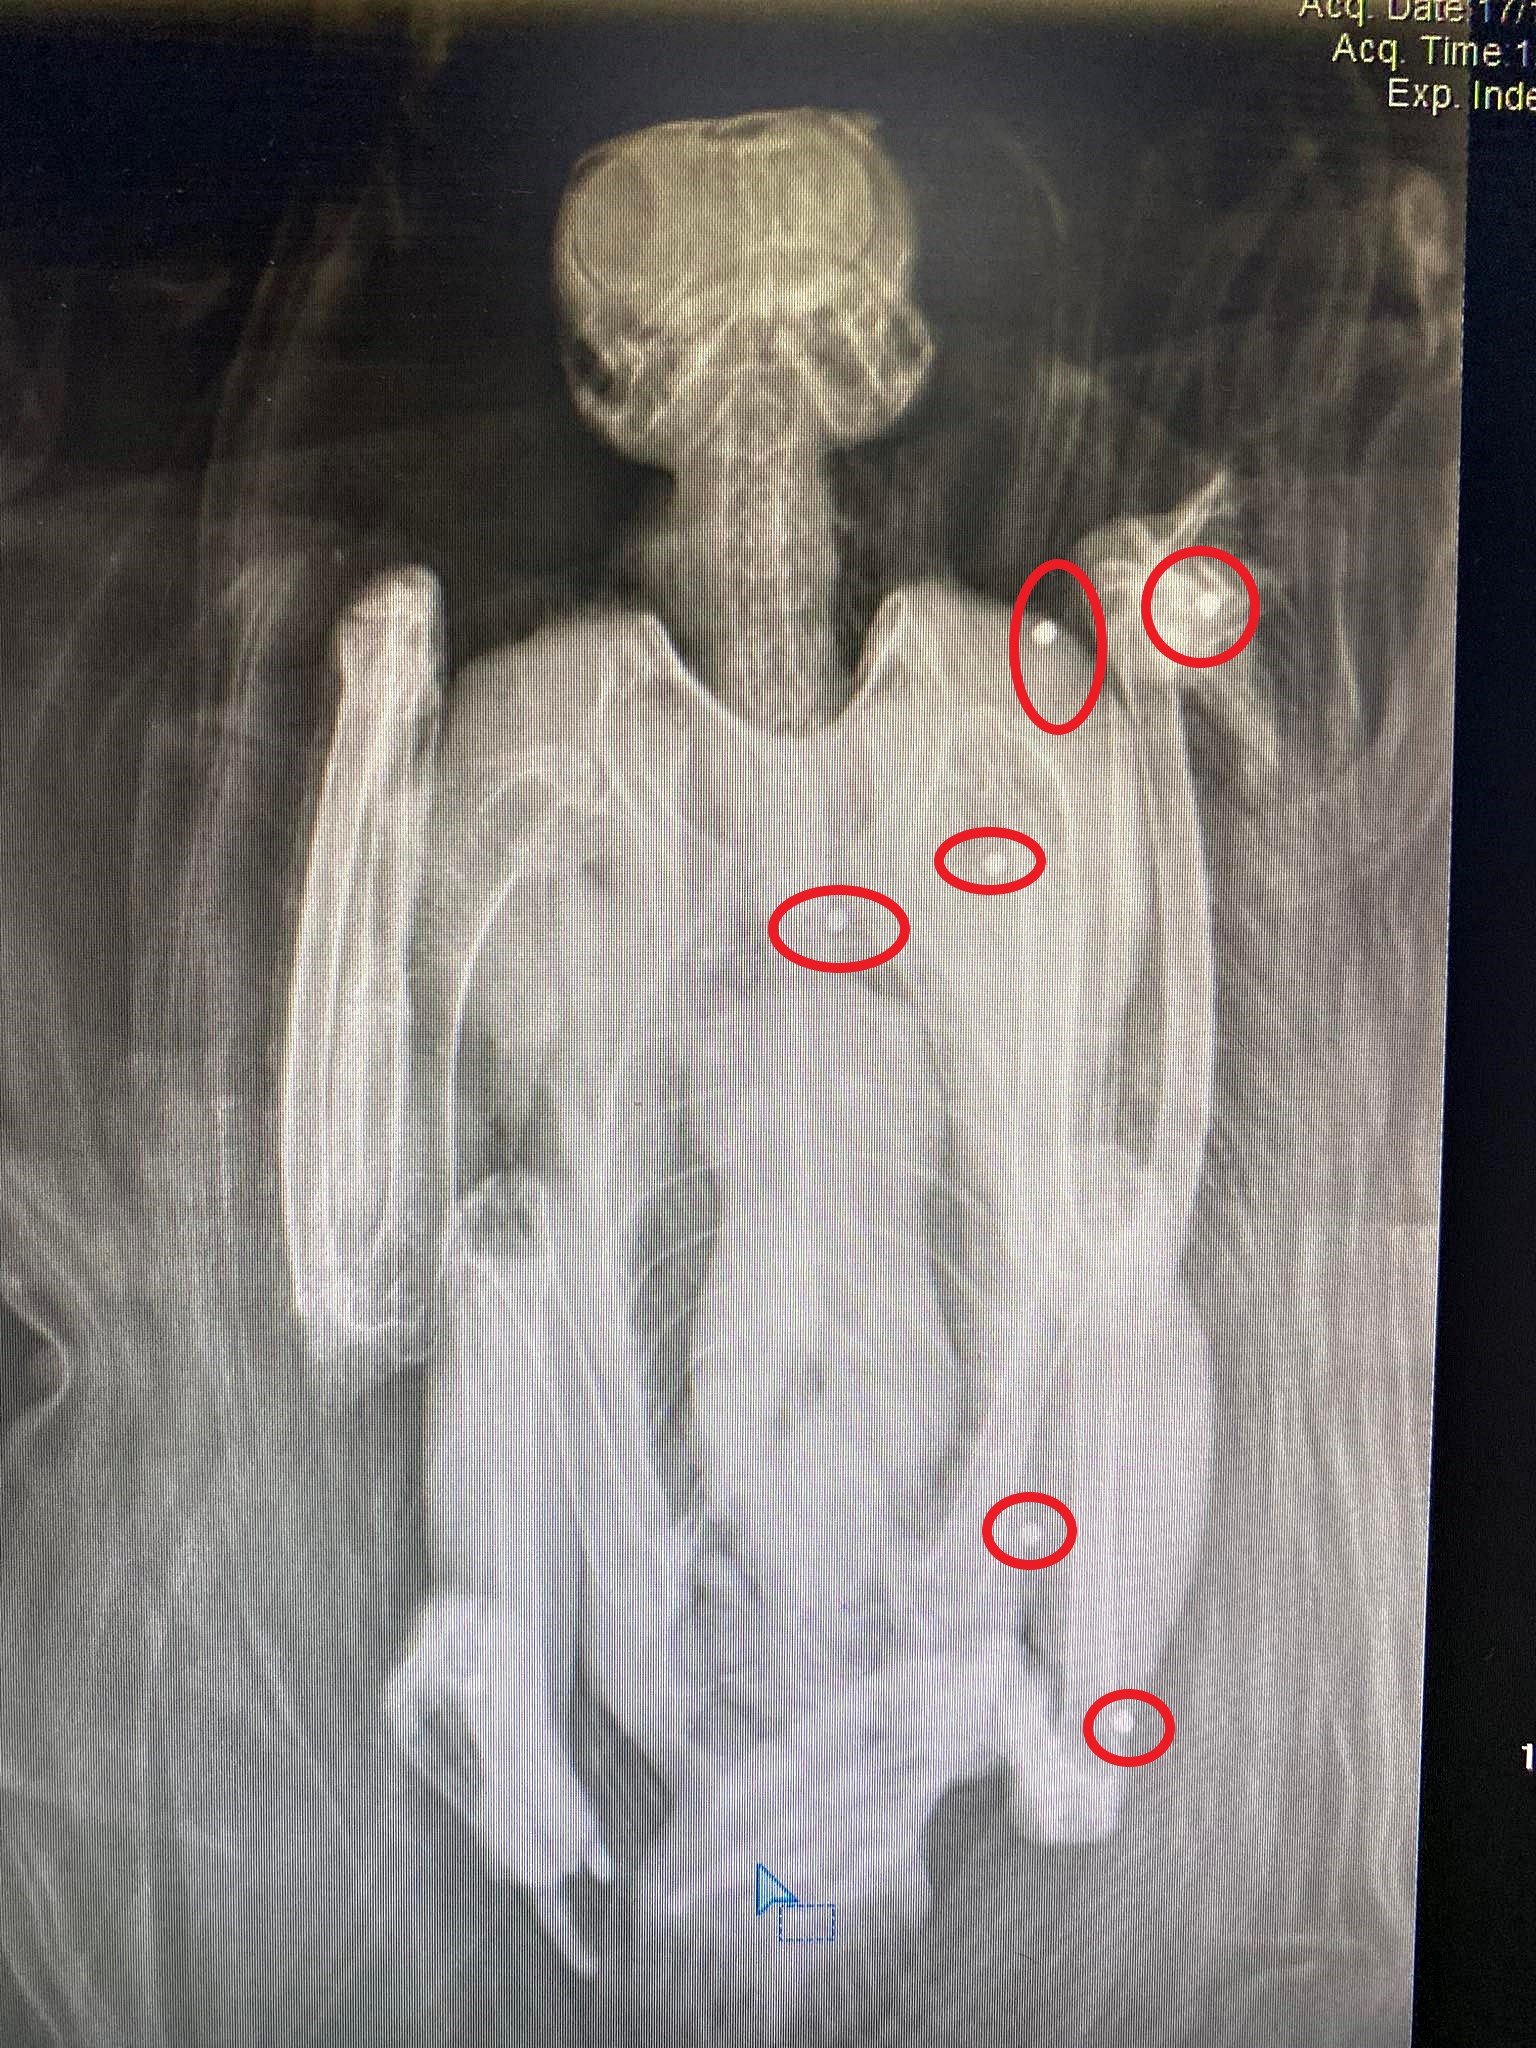

Αλγεινή εντύπωση έχουν προκαλέσει δύο περιστατικά με πυροβολημένα πουλιά που μεταφέρθηκαν πριν από λίγες μέρες στον Σύλλογο Προστασίας και Περίθαλψης Άγριας Ζωής.

Ο λόγος για έναν νεαρό πετρίτη και έναν πελαργό που εστάλησαν αντίστοιχα στις 8 και 12 Νοεμβρίου από το Δασαρχείο Χανίων, και τα δυο πουλιά πυροβολημένα.

Και με τόσο σοβαρά κατάγματα που δεν θα γυρίσουν ποτέ στην άγρια φύση, σύμφωνα με τους ειδικούς που εκφράζουν τον προβληματισμό τους...